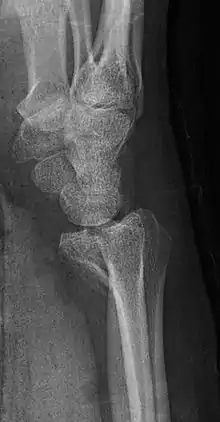

Lateral projectional radiograph of the same fracture

A Barton's fracture is a type of wrist injury where there is a broken bone associated with a dislocated bone in the wrist, typically occurring after falling on top of a bent wrist.[1] It is an intra-articular fracture of the distal radius with dislocation of the radiocarpal joint.[2]